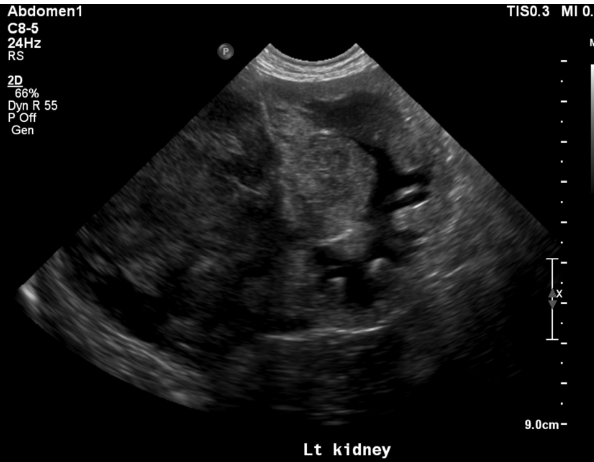

what is going on with this kidney

mass - neoplasia

focal/multifocal nodules with renal enlargement